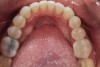

(4.) Preoperative occlusal view of upper arch.

Figure 4

A comprehensive examination was carried out, and preoperative photographs were taken (Figure 1 through Figure 4). The patient presented with fair oral hygiene and slight, generalized tissue inflammation. Caries and defective restorations were detected on teeth Nos. 4, 5, 13, and 14. The crown on tooth No. 12 was showing signs of leakage, and although the endodontic access cavity had been temporarily restored with composite, this endodontic re-treatment was acceptable and the tooth was otherwise symptom-free. Erosion was present on most of the posterior teeth and the cuspids, and abrasion was noted on teeth Nos. 4, 5, 10, 11, 20, 21, 22, 28, and 29. An examination of the patient's muscles, joints, and bite revealed no joint sounds, a normal range of motion, and negative joint load and immobilization tests.

The patient's removable dental orthotic covered the lower bicuspids and first molars. With the orthotic in place, there was shim stock contact on all posterior teeth and on the second molars that were not covered by the appliance. However, there was no incisal overlap and a lack of anterior guidance.11 When the orthotic was removed, solid shim stock contacts were present on the second molars and the right lateral incisor. These contacts were reproduced every time the appliance was removed. The same contacts were found on the patient's mounted models, which confirmed that the joints were in centric relation. Whether the lower second molars had overerupted as a result of wearing the appliance or had already been in this position before the orthotic was fitted could not be established. Apart from these three contacts, no other teeth touched, and there was a 2-mm space between the posterior teeth, making mastication difficult. Interestingly, wear facets were present on the palatal surfaces of the upper central and lateral incisors, indicating that at some point in time, there had been significant overlap of the anterior teeth and a possible constriction of the chewing envelope. Analysis of a cephalometric radiograph showed a class II growth tendency with a reduced mandibular plane angle, which supported the theory that the patient had at one time possessed a class II occlusion.